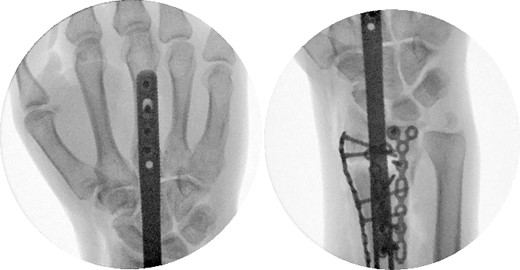

A dorsal spanning plate was planned to treat the fracture. An incision was made over the third dorsal compartment followed by release of the fourth dorsal compartment to fully visualize the fracture. Once the plate was placed, intraoperative fluoroscopy revealed that that radial styloid was still displaced. After releasing the first dorsal compartment and brachioradialis, a radiostyloid plate was then placed. Additionally, the volar ulnar corner of the radius was still not reduced properly, so a Protean fragment specific volar buttress plate was placed. Final intraoperative fluoroscopy films revealed satisfactory reduction and alignment (Figs 3 and 4).

Two weeks following the procedure, the patient returned to the clinic for a follow-up visit. The wrist was swollen and ROM was limited. Hand motor functions and neurovascular exam were fully intact. Radiographs taken in clinic showed intact hardware with healing fracture. At 2 months follow-up, radiographs showed intact hardware with interval bone bridging across fracture sites. Radiographic parameters including articular alignment, radial height, radial inclination, and volar tilt were in acceptable ranges (Fig. 5). The patient reported no concerns or complications. A computed tomography (CT) scan was obtained at 10 weeks after the procedure and confirmed adequate bony healing and alignment without failure (Fig. 6). The dorsal spanning plate was eventually removed 1 month later and 4 months since the initial operation (Fig. 7).